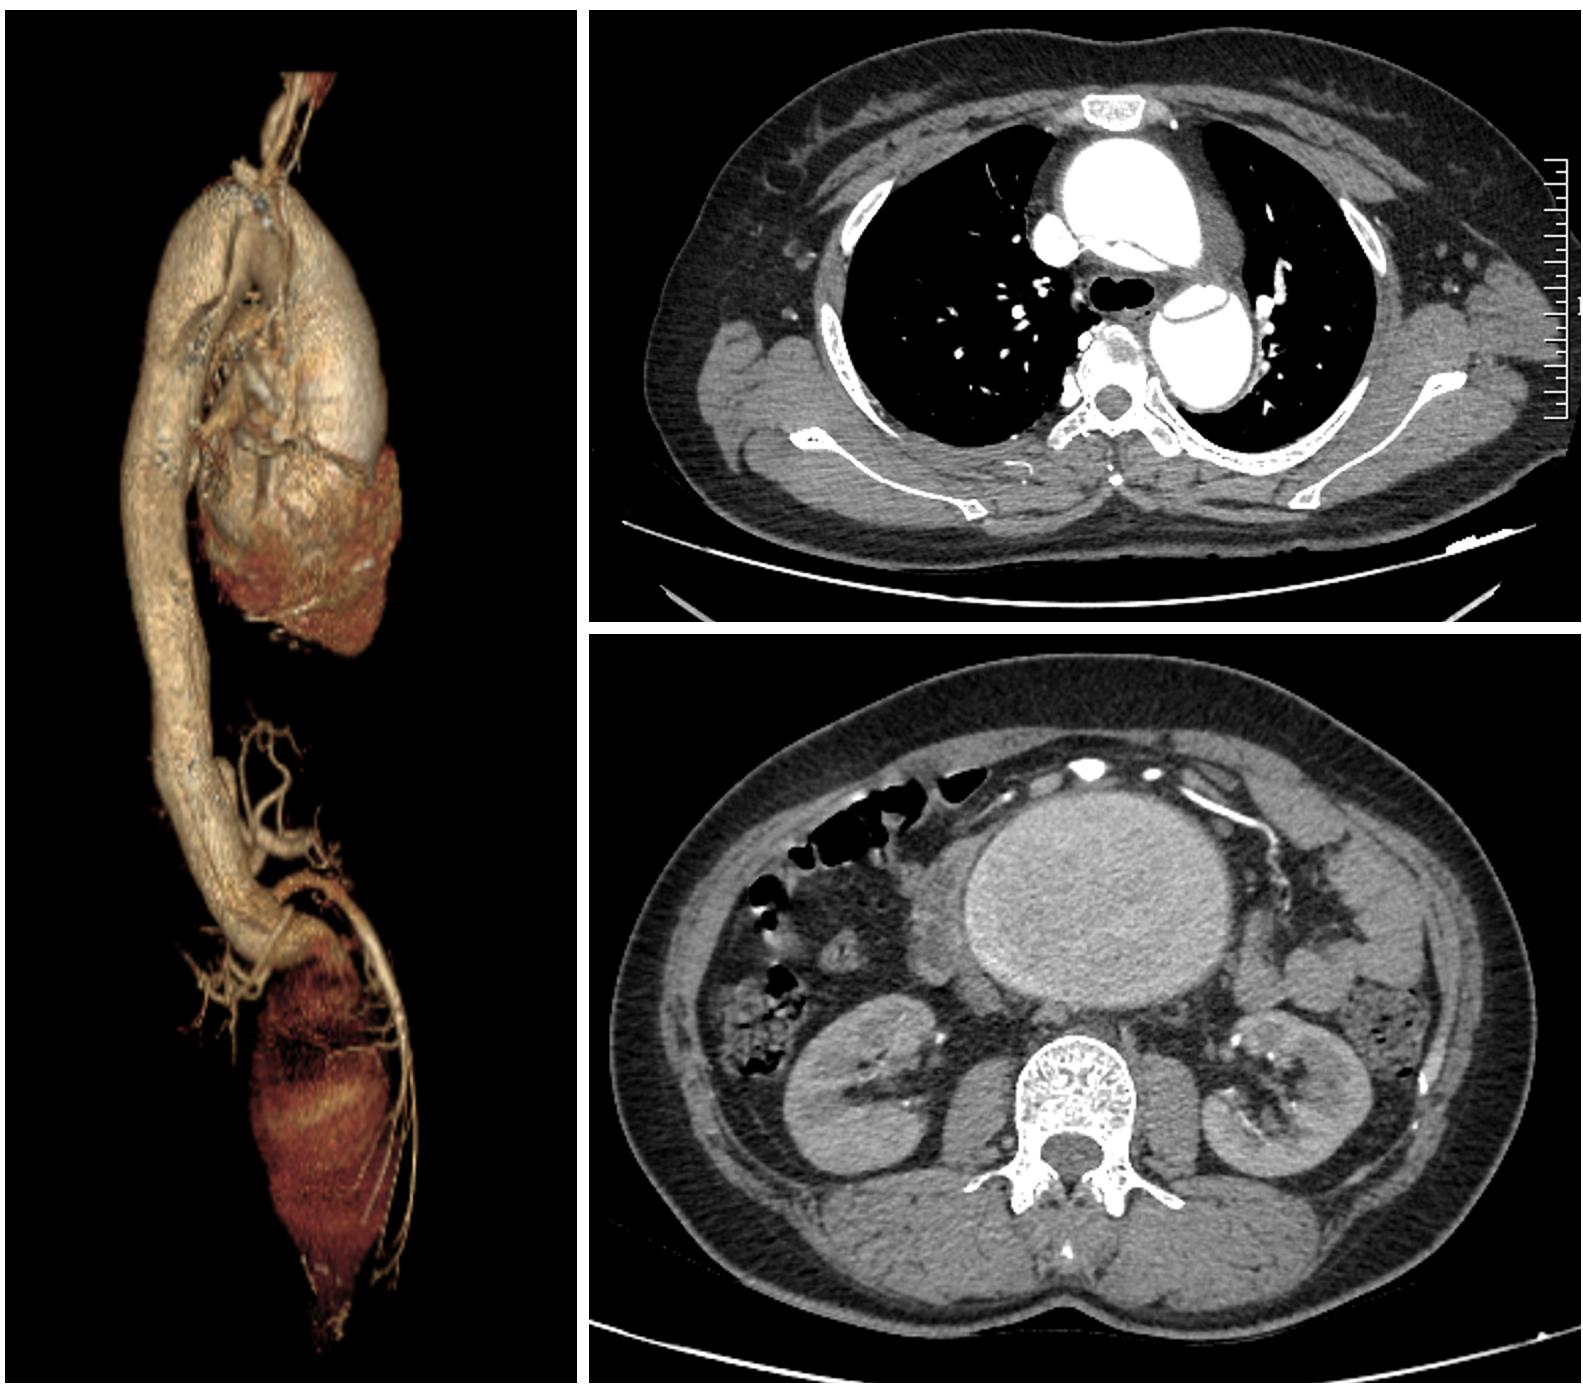

检查结果犹如晴天霹雳!CT 显示,张英同时罹患两大致命疾病:A 型心脏主动脉夹层和巨大腹主动脉瘤。

此外,张英体内还藏着另一颗随时可能引爆的「炸弹」:直径长达 9.3 厘米的巨大腹主动脉瘤。一般情况下,直径超过 5 厘米,破裂风险就很高了;而腹主动脉瘤一旦破裂,也同样没有抢救机会。

尽管 A 型主动脉夹层是创伤最大的手术,被公认为是外科手术的「皇冠」,但在武汉大学人民医院心血管外科,这已经是常规操作:先手术替换升主动脉和主动脉弓,同时在降主动脉处植入支架,而降主动脉以下的病变会留待若干年后二期手术处理。但张英还合并有巨大腹主动脉瘤,破裂风险极高,她的腹主动脉段病变根本不可能留到将来再处理。

要想拯救生命,尽快根治这两大致命疾病,唯一的办法就是将 1 米长的人体主动脉血管全程替换为人工血管。然而,主动脉与心脏连接,经由胸部、腹部,终止于双髂动脉,这项手术将涉及人体所有的重要器官:心脏、脑、脊髓、肺、肝、肾和胃肠的血管和神经保护,手术时间长、创伤大、出血多,术后并发症和死亡率高,是国际主动脉外科领域最复杂的手术。

习惯于挑战常规、勇于创新的王志维教授,决定为了患者的生命,再度冒险。心血管外科团队精心筹划,制定了缜密的救治计划。拟定的手术分两次进行:第一次手术正中开胸替换主动脉瓣、升主动脉、主动脉弓,并在降主动脉植入象鼻支架;第二次手术,从右胸经腹部到左侧大腿根部开超长切口,替换胸降主动脉、腹主动脉,重建脊髓、双肾、肝脏、肠道、双下肢血流。